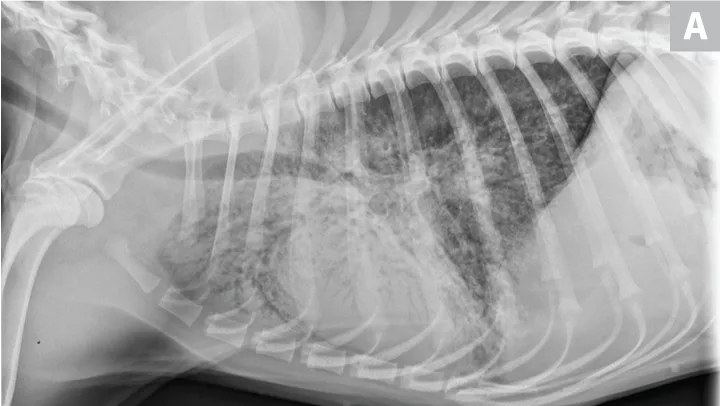

CDV should be suspected in poorly vaccinated dogs with multiorgan involvement. Dogs with CDV may have exhibited only respiratory signs before developing characteristic nonrespiratory signs.12 Radiographs may reveal a diffuse interstitial pattern (Figure 2). Diagnosis is supported by compatible clinical signs and complementary diagnostic testing (ie, real-time reverse transcription polymerase chain reaction [RT-PCR], serology, CSF pleocytosis). Conjunctival scraping and tissue-based immunohistochemistry may confirm diagnosis.

FIGURE 2

CDV pneumonia with a diffuse interstitial pattern confirmed by multisystemic signs, urine RT-PCR, and necropsy